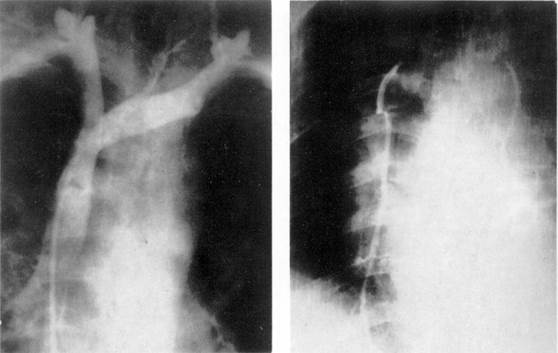

лобулярные ветви легочной артерии). Рис. 8.

Верхняя кавография.

Контрастированы

верхняя полая вена, безымянная вена и правое предсердие.

Рис. 9.

Флебограмма

внутренних грудных вен.

Верхняя кавография наиболее часто выполняется путем пункции локтевых вен или их катетеризации. Другим вариантом верхней кавографии

является ретроградная катетеризация верхней полой вены через нижнюю полую вену и правое предсердие. При введении контрастного вещества регистрируется продвижение его по венам переднего средостения, а также сосудам малого круга (рис. 8).

Контрастное исследование внутренних грудных вен выполняется введением контрастного вещества в грудину на уровне четвертого межреберья.

На флебограммах

внутренние грудные вены видны в виде двух контрастируемых

сосудов, расположенных параллельно обеим сторонам грудины (рис. 9). Признаками, указывающими на наличие увеличенных лимфатических узлов парастернальной

области, считают локальные сужения просвета вен вплоть до полного блока, появление ретроградного кровотока,

коллатеральных ветвей, участков расширения вен на ограниченном протяжении.